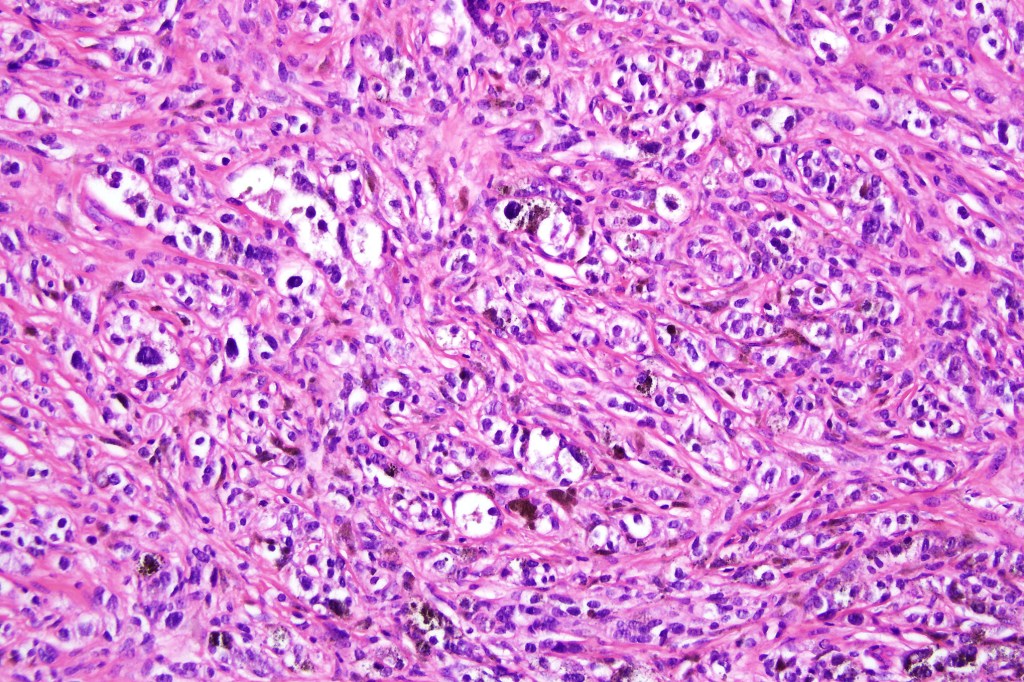

•Enlarged cells with copious eosinophilic, foamy or clear cytoplasm (some authors include melanoma with clear cell change in the same category)

•Variable pigmentation

•Nuclei vesicular or hyperchromatic

•Pleomorphism is not generally marked and indeed can be very subtle

•Variable mitotic activity

•DPAS granules

•Thought to be a result of abnormal or degenerative melanosome change